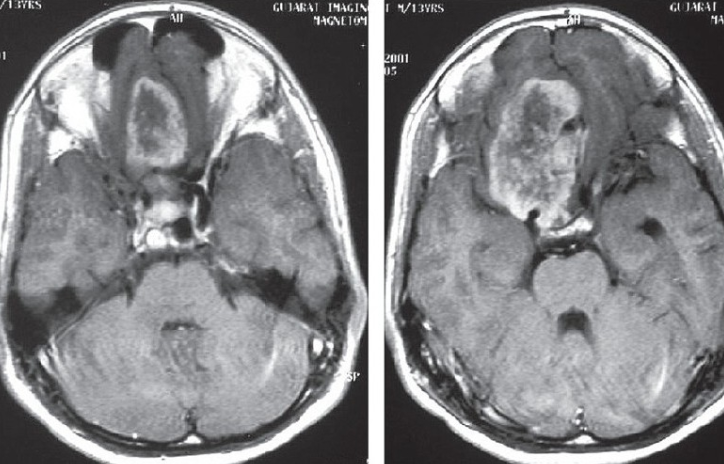

1、脑部CT

显示轴内或轴外肿块伴骨质破坏,肿瘤通常是高密度肿瘤周围水肿,但很少或没有钙化。

2、脑MR

在T1加权成像中显示出模糊的肿瘤边缘,浸润性肿瘤与正常的脑实质关系密切。T2WI和FLAIR图像显示肿瘤周围水肿,强化后可肿瘤增强,甚至侵犯颅骨和头皮,MRV可能显示硬脑膜窦侵犯。